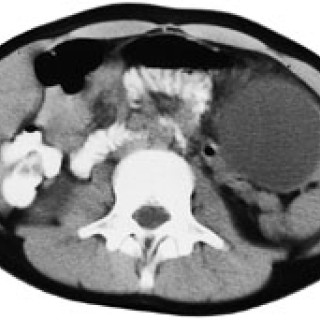

Pasientar med akutt innsetjande brystsmerter er ei stor diagnostisk utfordring. Symptomet kan oftast tilskrivast kardiovaskulære, pulmonale, muskel- og skjelettopphavelege eller psykiske lidingar, men tilstandar i gastrointestinalkanalen kan o†g gje opphav til dette symptomet. Spontan oesophagusruptur, også kalla Boerhaaves syndrom, er ei høgst uvanleg årsak til akutte brystsmerter. Pasienten . Mann, fødd i 1912, budde heime og hadde tidlegare stort sett vore frisk, men fekk i 2000 innlagt permanent kateter pga. urinretensjon. Ein dag i april 2001 då han skulle ete middag, fekk han akutt...